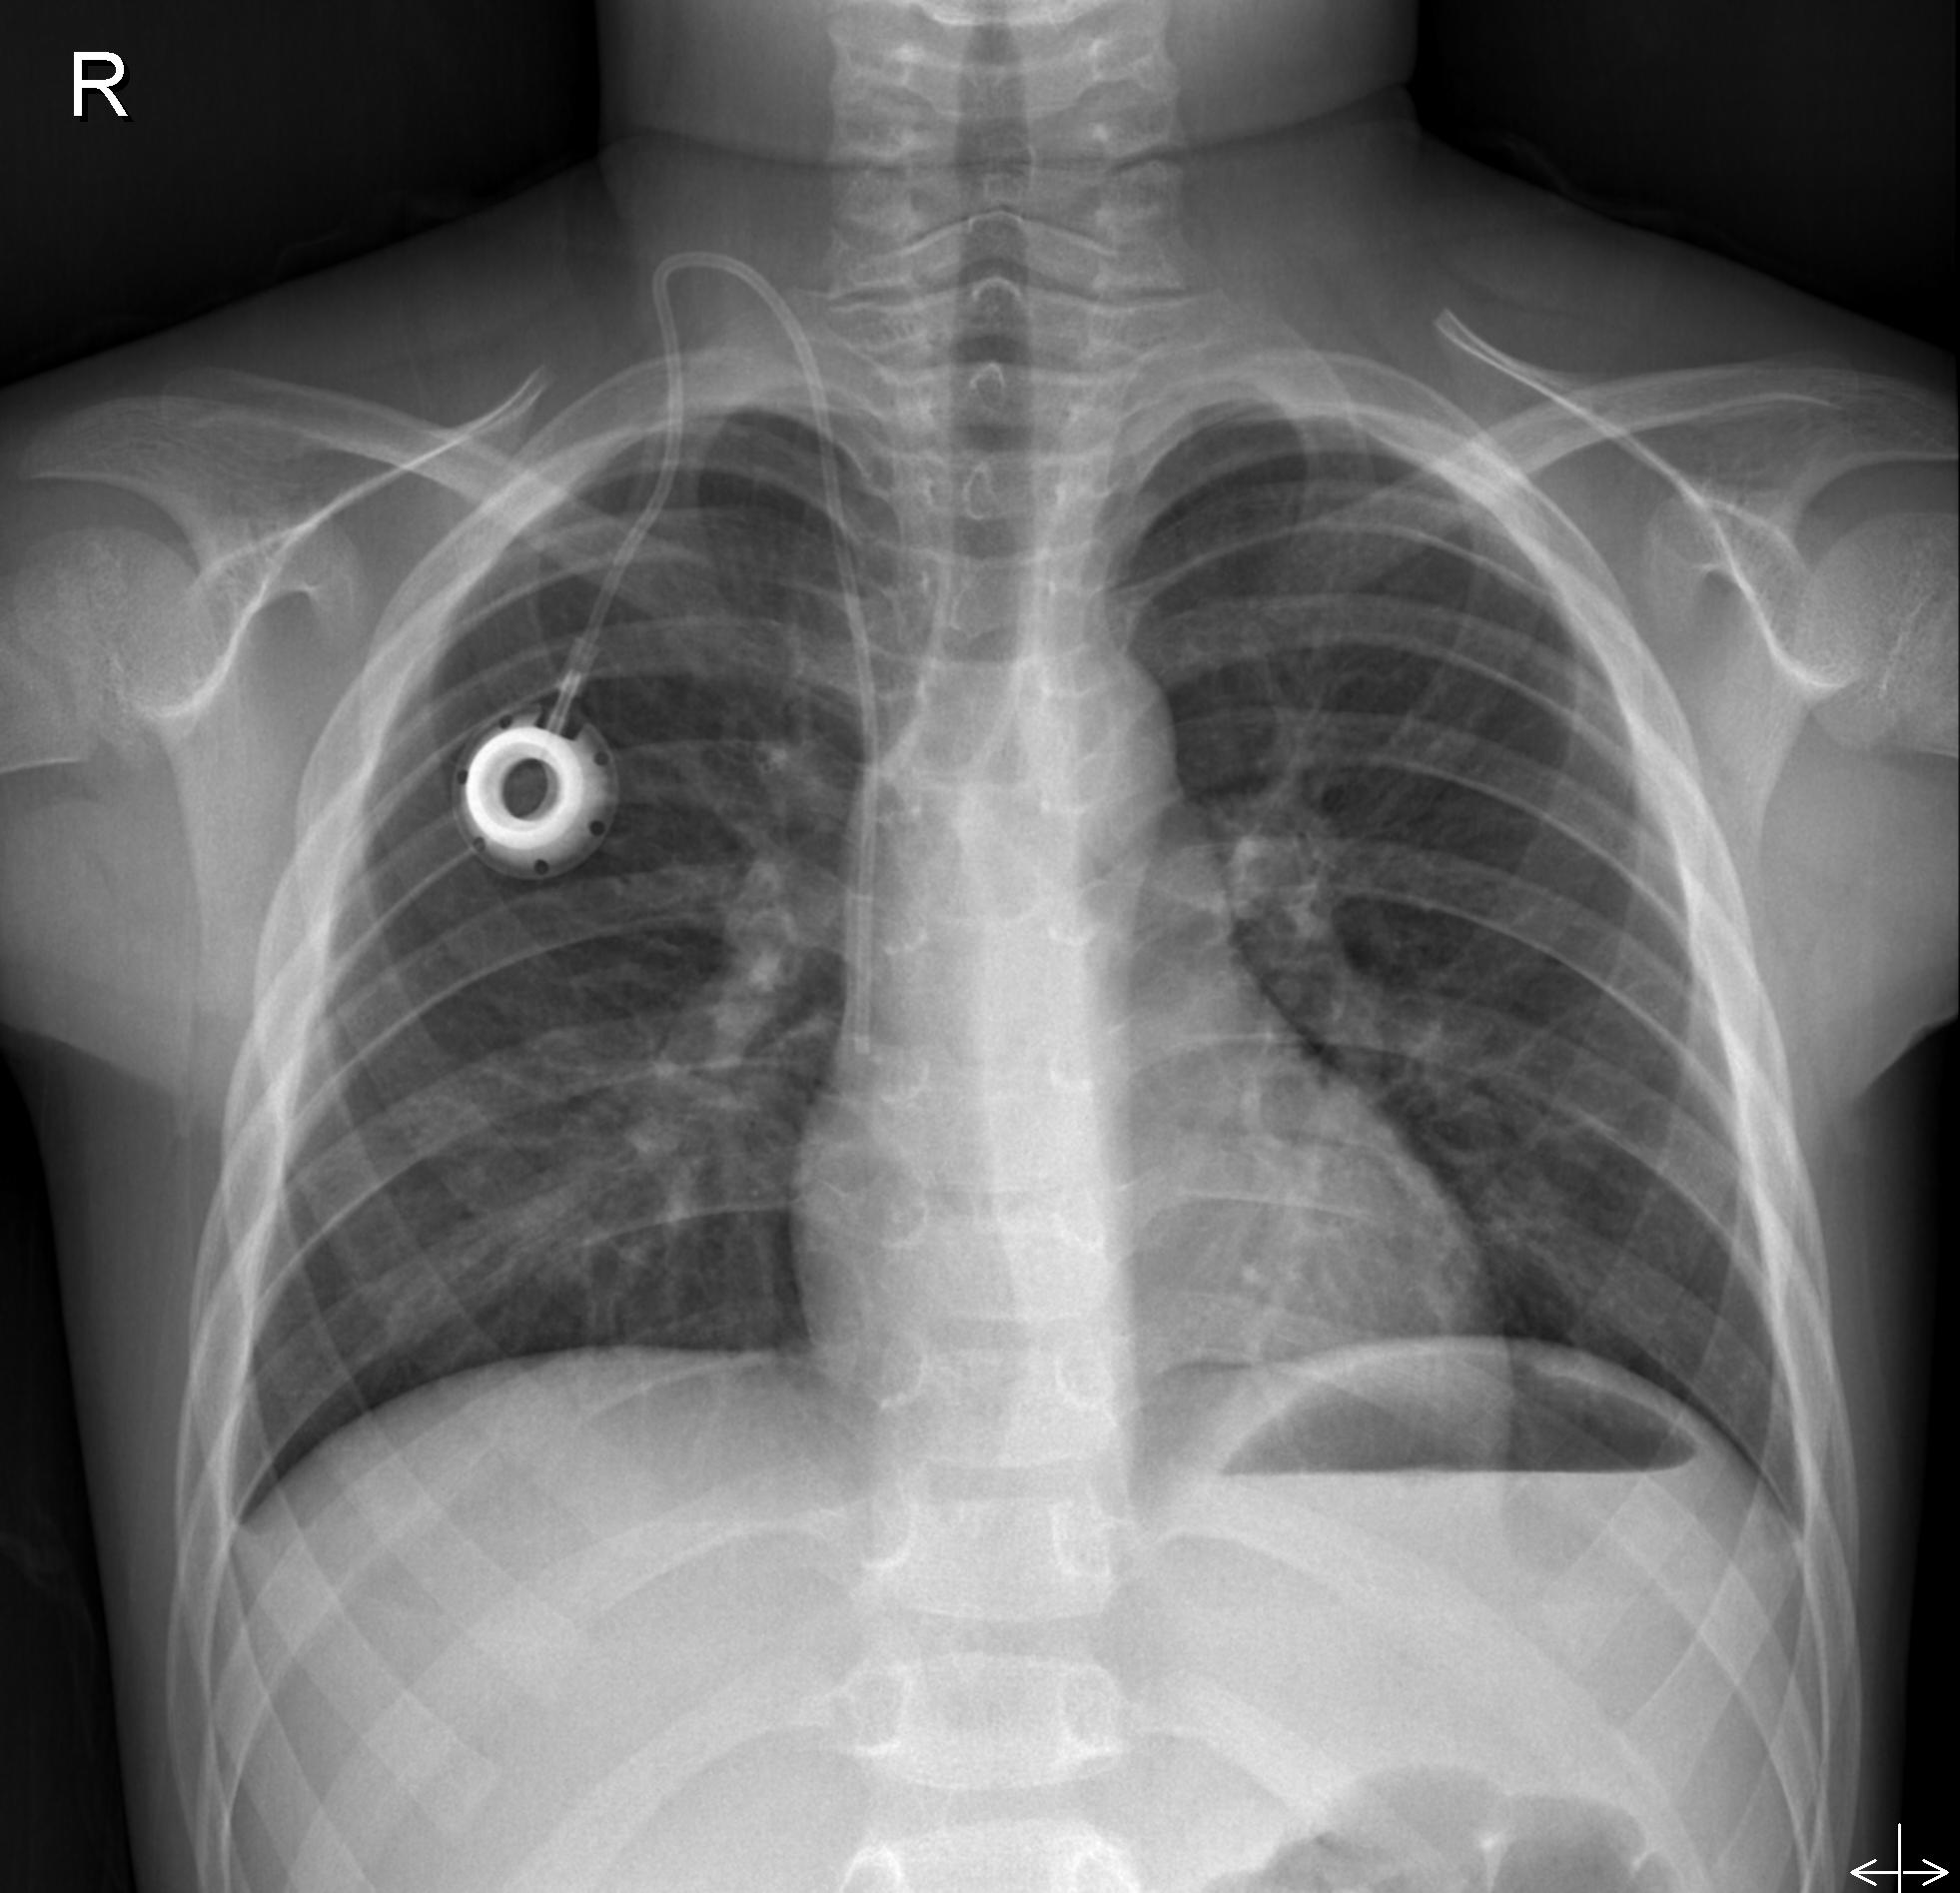

주기적인 화학치료 때문에 그림에 보이는 CHEMO PORT나 HICKMAN CATHETER를 갖고 있답니다.